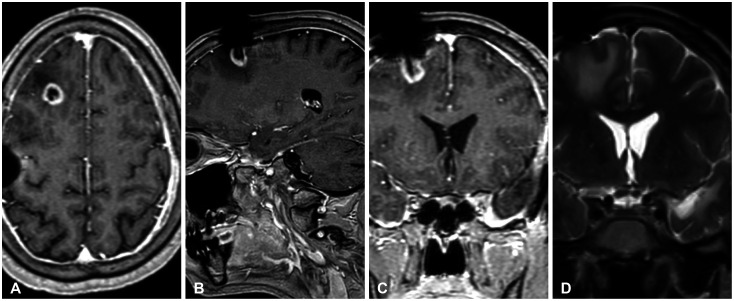

Glioblastoma multiforme (GBM) is the most common primary brain tumor in adults with a median survival of approximately 15 months, despite treatment, with most patients experiencing recurrence within 9 months of resection. The propensity of recurrence in GBM exemplifies the fatal course of the disease and remains an underlying area of study as novel instances of recurrence are encountered. The authors present a unique case of a 31-year-old male patient with a history of cerebellomedullary junction astrocytoma who later developed a supratentorial GBM followed by recurrence centered around a preexisting ventriculoperitoneal catheter and located in the hemisphere contralateral to his first GBM. Each of these lesions was initially thought to represent de novo glial neoplasms because of the absence of intervening T2 fluid-attenuated inversion recovery signal change between each lesion. However, next-generation sequencing using the GlioSeq™ platform revealed similar mutational profiles in both GBMs, suggesting an alternative method of migration of tumor cells to the shunt catheter site, and a local inflammatory environment likely triggering recurrence. This study concludes that in rare instances, in the presence of dormant glioma cells, intracranial foreign bodies may promote an inflammatory microenvironment that may activate tumorigenesis.